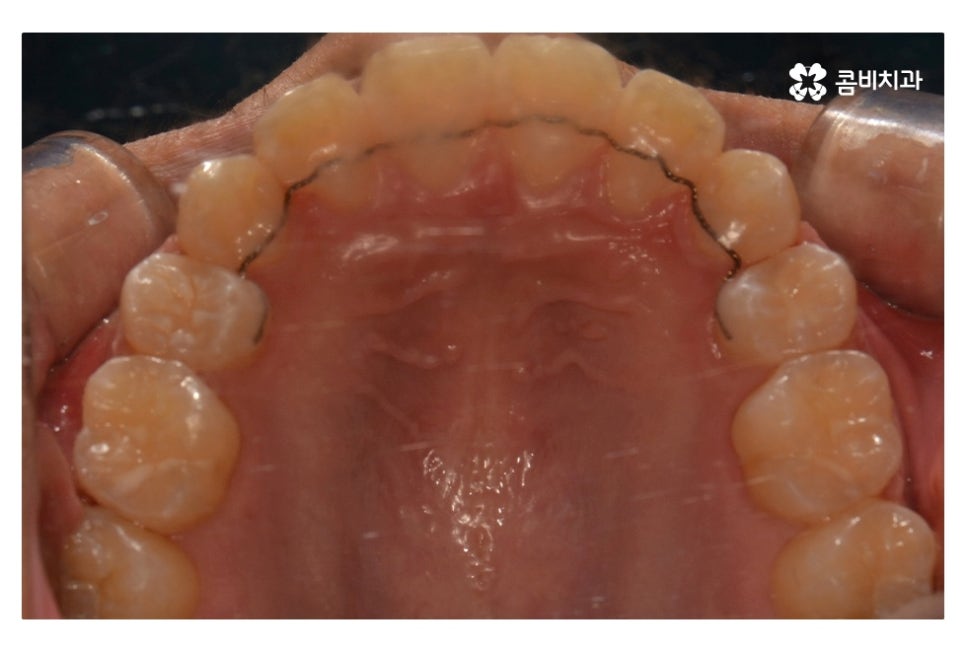

오늘 보여드릴 중학생치아교정 사례의 경우에는

악골의 위치는 정상적인 상태에서 불규칙한 치열로 인해

교정 치료를 진행한 사례라고 할 수 있어요.

위 환자분의 경우 발치가 진행된 사례로 치아의 이동 공간을

고려할 때 발치가 필요했고 환자분도 보다 나은

심미성을 위해서 동의한 상황이라고 할 수 있어요.

위 사진에서 보시면 시간이 지나면서 발치를 했던 치아의

공간이 사라지고 교정을 통해서 치열이 가지런해진 것을 확인할 수 있는데요.

중학생치아교정에 있어서 중요한 사항이 단지 치열만이

가지런해 보이는 것이 아닌 얼굴과의 조화와 교합이라 할 수 있어요.